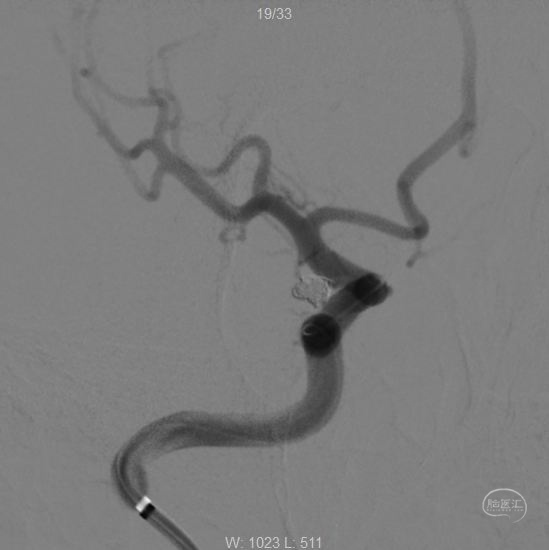

解脱第一枚弹簧圈,经过微导管1,继续填塞,二维Target2-4、APB1.5-4-3D-ES、APB1.5-2- HX-ES、APB1-4-3D-ES各一枚。

撤出微导管1,可见该微导管占据的缝隙,此处仍空虚。

造影

继续经过微导管2植入:APB1-3-3D-ES、二维Target1-2各一枚。